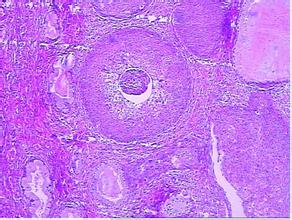

某些慢性皮肤病,如寻常狼疮、红斑狼疮、黏膜白斑、慢性溃疡或窦道、烧伤瘢痕、射线皮炎、慢性肉芽肿疣状表皮发育不良、慢性骨髓炎、萎缩硬化性苔藓等均可诱发或继发鳞癌。

某些癌前期皮肤病如日光角化病、黏膜白斑、砷角化病、X线和镭射线性皮炎等均易致鳞癌。以及其他慢性皮肤病,如疣状表皮发育不良、慢性溃疡、慢性窦道、慢性骨髓炎、慢性红斑狼疮、寻常狼疮、萎缩硬化性苔藓等均可诱发或继发鳞癌。